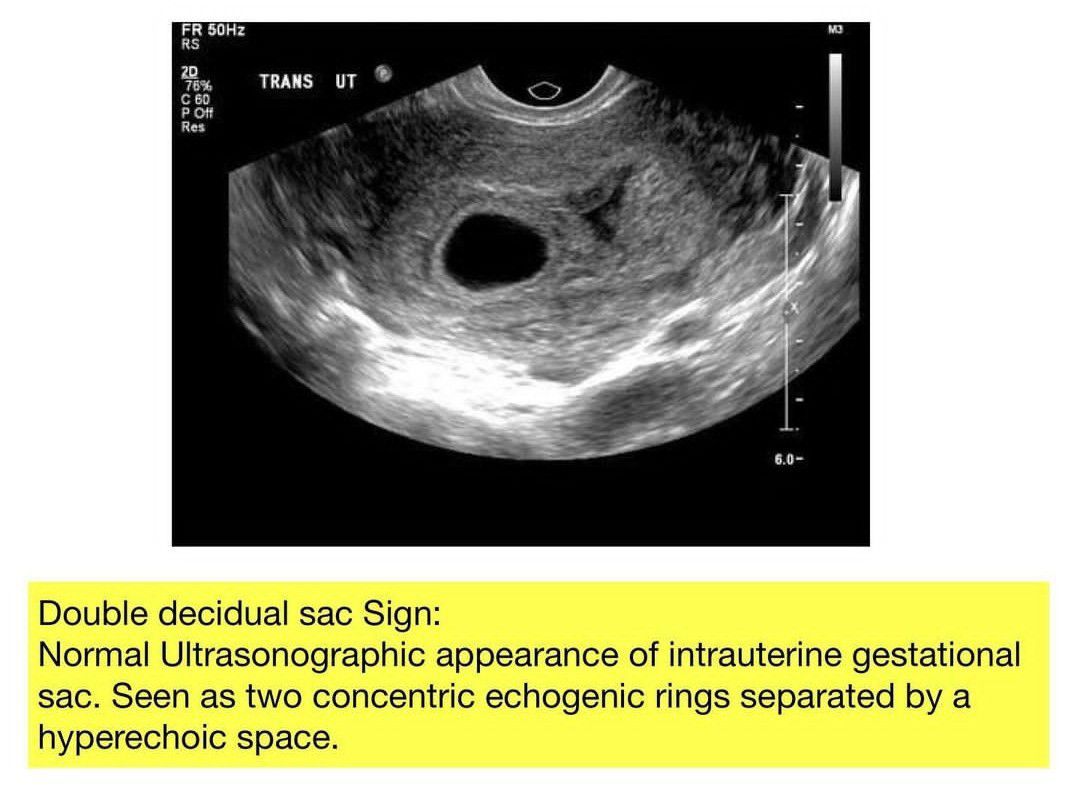

Double Decidual Sac Sign

Here is a review of the double decidual sac sign.